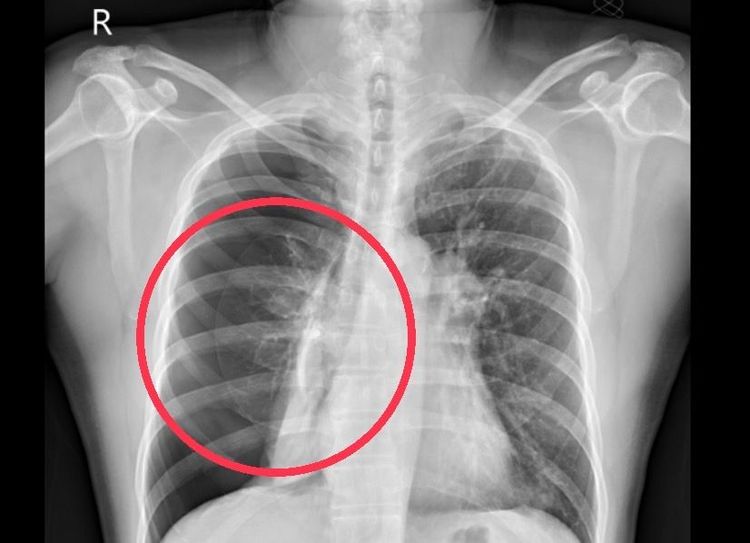

照片X光片的紅圈處為患者右肺明顯塌陷。南投醫院提供

南投醫院胸腔內科主任施志宏指出,氣胸是指空氣堆積於肋膜腔內,使肺葉塌陷。可能會有胸悶、胸痛、呼吸困難、喘等症狀,嚴重時會引發張力型氣胸,導致休克甚至死亡。